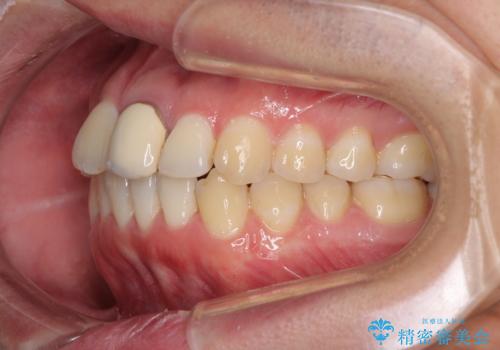

前歯の歯並びとクラウンを改善 インビザラインとオールセラミック

- 前歯の歯並びと不自然な色をした前歯のクラウンを気にして来院された患者様です。

上下前歯の歯列不正はインビザラインにより歯列を整え、その後に、前歯をオーダーメイドタイプのオールセラミッククラウンにて補綴治療することとしました。

初診時には、歯並びを整えることのみを検討されていましたが、歯列が整うにつれて不自然な色合いが気になるようになり、矯正治療を行ってから補綴治療をする計画を受け入れてくださいました。

口元の印象が明るく変わり、患者様には大変満足していただきました。